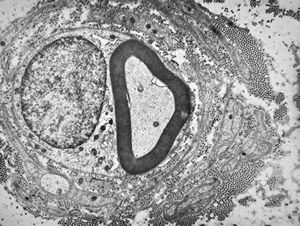

F,12y. | hypertrophic (onion bulb) neuropathy - n.suralis